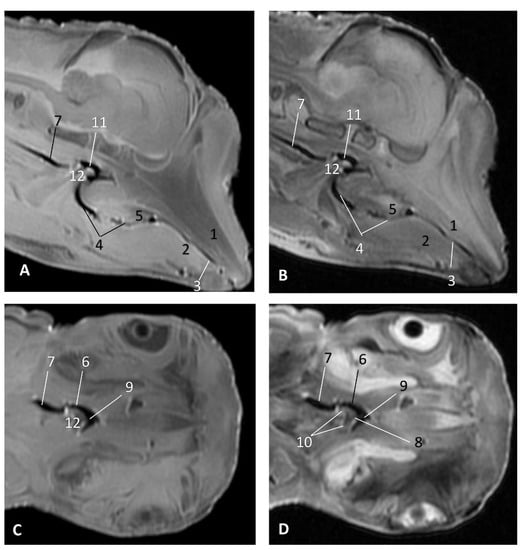

In MRI, we can appreciate, in early fetal stages, a bilateral structure within the laryngopharyngeal cavity, each named as a pharyngeal diverticulum of the auditory tube (PDAT). These are connected through the musculotubaric channel with the middle ear (temporal bone: petrous and tympanic part). In a young Delphinus delphis fetus (dde3), it appears in sagittal sections as a hyper/hypointense area seen caudal and rostrally, respectively (Figure 26A,B), and also in coronal sections (Figure 26C,D).

Figure 26. Images of the pharyngeal cavity. MR sagittal and coronal images are oriented so that the rostral is to the right. (A) T1 SE sagittal, (B) T2 FrFSE sagittal, (C) T1 SE coronal and (D) T2 FrFSE coronal planes. 4 months, dde3. 1, Inner and middle ear; 2, Pharyngeal diverticulum of the auditory tube.